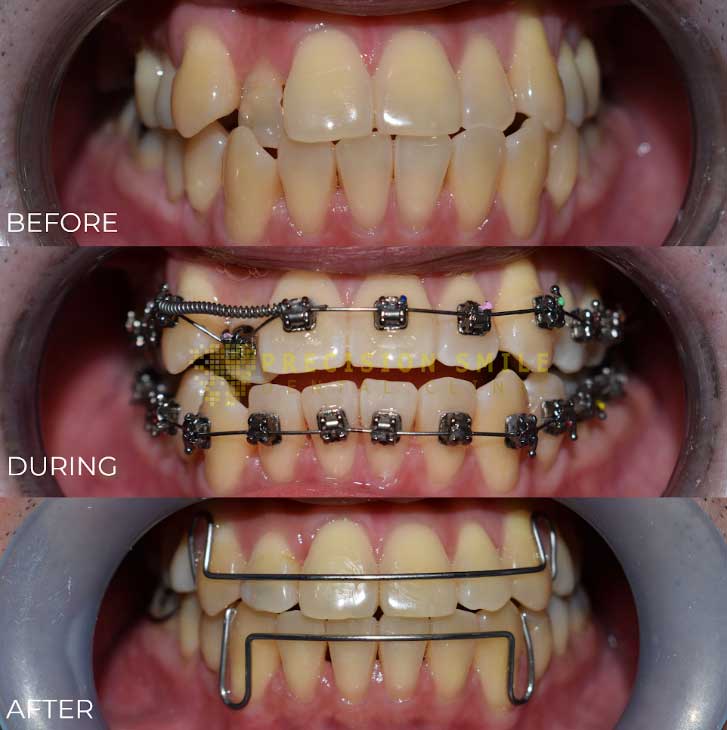

Metal braces are the most common and widely used orthodontic treatment. Made of durable stainless-steel brackets and wires, they effectively straighten teeth. Patients can customize their braces with colorful bands, making treatment both functional and fun.

The SWLF® System features a unique low-friction passive/active bracket and innovative super-elastic wires for faster, more comfortable treatment. This system reduces treatment time by up to 30% and minimizes the number of dental visits, making it an efficient choice for orthodontic correction.

Self-ligating braces use a specialized clip instead of elastic bands to hold the wire in place. This design reduces friction, allowing for a more comfortable and efficient treatment process with fewer orthodontic visits. They are available in metal, ceramic, or clear materials.